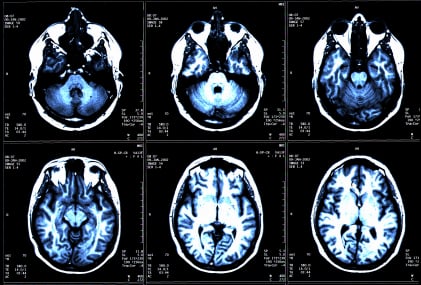

Essa attraversa la barriera ematoencefalica, si lega a neuroni di due zone del cervello (il mesoencefalo e l’ippocampo) e così facendo favorisce la sintesi della serotonina e delle catecolamine, frena la sintesi del neurotrasmettitore inibitore GABA e favorisce la neurogenesi adulta,vale a dire la proliferazione di nuovi neuroni anche in età adulta, un concetto negato fino agli anni Sessanta del secolo scorso.

E’ quindi un aiuto alla rigenerazione del cervello. La seconda funzione dell’osteocalcina è quella di essere necessaria allo sviluppo di altre due parti del cervello: il corpo calloso e l’ippocampo, essenziale per la memoria.

L’esperimento sui topi ha mostrato che i soggetti deprivati di osteolcalcina erano più ansiosi e depressi, e che non avevano affatto memoria. Con un’infusione di osteocalcina, che ha corretto completamente la sintesi dei neurotrasmettitori, sono scomparse l’ansietà e la depressione, e la memoria è stata in parte ritrovata. E si è visto chiaramente che l’osteocalcina ha una doppia funzione: pre e post-natale. Prima della nascita, è sintetizzata dalla madre e passa al feto, dando origine allo sviluppo di quelle parti del cervello che presiedono alla memoria.